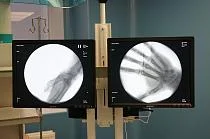

Помимо оперблока участники рабочего выезда осмотрели обновленный травмпункт, в котором также провели капитальный ремонт и закупили еще один рентген-аппарат стоимостью 14,8 миллиона рублей по региональной госпрограмме развития здравоохранения.